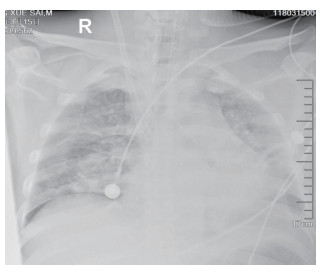

1.2 临床表现和检查患者初期有咳嗽症状,但未在意,患者回家24 h后咳嗽症状加重,伴胸闷气喘,全身大汗淋漓,家属立即将其送至本院急诊,为进一步诊治拟“有机氟中毒”收住入院。入院时体检:神志清楚,T:36.5℃,R: 57次/min,BP: 146/71 mmHg,胸廓对称无畸形,呼吸急促,听诊双肺呼吸音清晰,可闻及大量湿性啰音,心率112次/min,心律齐,心音正常,各瓣膜听诊区未闻及病理性杂音及心包摩擦音,四肢关节正常,双下肢无水肿,深浅生理反射正常,病理反射阴性,脑膜刺激征阴性。辅助检查:白细胞计数10.45×109/L,中性粒细胞91.9%;C-反应蛋白14.81 mg/L, 无创机械通气支持下血气分析pH7.28,PCO2 50 mmHg, PO2 57 mmHg, Lac 3.0 mmol/L(FiO2 50%),为Ⅱ型呼吸衰竭,给予无创呼吸机辅助呼吸、激素冲击、解痉平喘等抢救治疗。急诊胸部CT检查提示:两肺散在斑片状模糊影,密度不均,边界不清(图 1),进ICU床边胸片提示:两肺散在斑片状模糊影(图 2)。根据GBZ5—2016《职业性氟及其无机化合物中毒的诊断》的诊断标准,该患者诊断为职业性急性重度有机氟中毒。

| 图 2 3月10日胸部X线 |